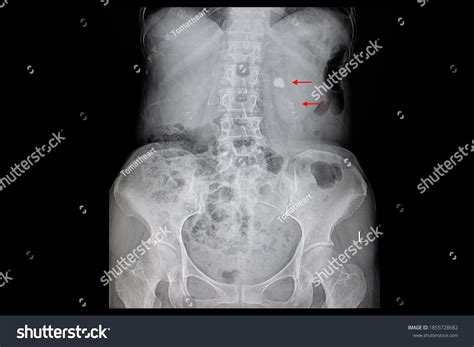

A Kub Abdominal X Ray, also known as a KUB (Kidneys, Ureters, Bladder) X-ray, is a type of abdominal radiograph that provides a detailed view of the abdominal cavity. This imaging technique is commonly used to assess the organs and structures within the abdomen, including the kidneys, ureters, bladder, intestines, and other soft tissues. The primary goal of a Kub Abdominal X Ray is to detect abnormalities such as obstructions, infections, or tumors.

• Calcifications or stones in the kidneys or bladder

Kidney Stones Calcifications in the kidneys that can cause severe pain and urinary tract infections.